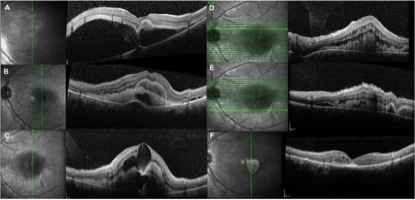

图 1 急性期和终末期的 OCT 表现

初次检查时 OCT 可见黄斑区视网膜神经感觉层大量浆液积聚,中央视网膜下高反射物质,BCVA 为 20/200(图 1-a)。

随访 1 周时 OCT 可见视网膜下液体及双层物质,可能由视网膜下纤维蛋白渗出有关,BCVA 为 20/200(图 1-b)。

随访 1 月时眼底 OCT 可见巨大黄斑囊样间隙以及表现为多灶性高反射区的黄斑下渗出可见,掩盖了深层隐约可见的视网膜色素上皮层上方的反射物质,BCVA 为 20/250(图 1-c)。黄斑上方及下方 OCT 可见视网膜下渗出,视网膜囊样间隙(图 1-d-e)。

分娩后检查 OCT 可见视网膜下纤维蛋白渗出吸收,视网膜外层严重损害,黄斑下纤维化,BCVA 为 20/250(图 1-f)。